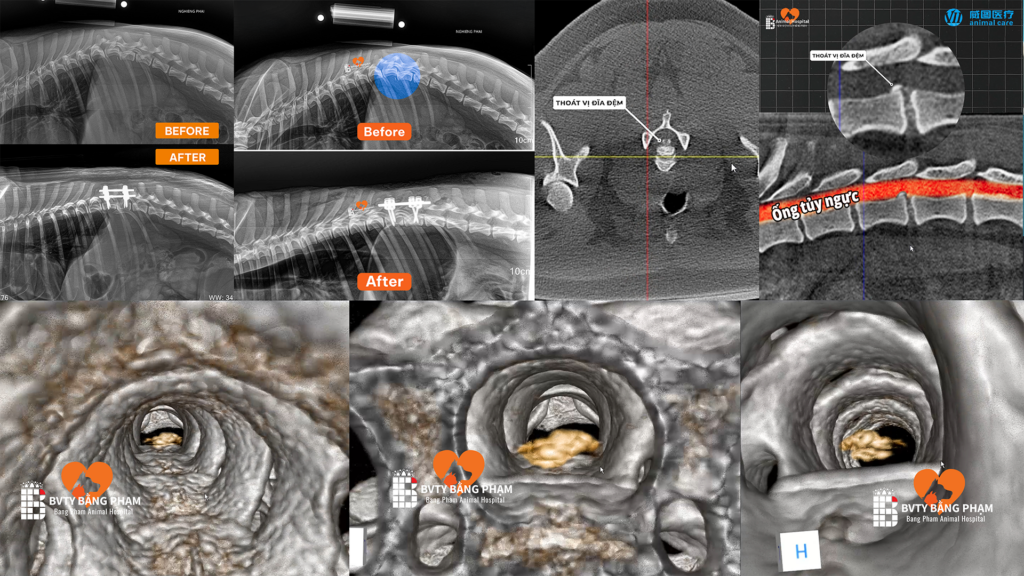

- Dịch Vụ Chụp CT Scan Thú Y – Thực hiện bằng máy CBCT Vetoo, thiết bị hiện đại có chức năng chụp CT chuyên dụng cho thú y, cho phép tái tạo hình ảnh 3D độ phân giải cao của xương, khớp, răng, não và các cơ quan nội tạng.

Nhờ công nghệ Cone Beam CT (CBCT) tiên tiến, hình ảnh thu được chi tiết hơn, giúp bác sĩ đánh giá chính xác tổn thương, phát hiện bất thường sớm và lên kế hoạch phẫu thuật an toàn, hiệu quả cho thú cưng.

Dịch Vụ Phẫu Thuật Thần Kinh – Cột Sống

Can thiệp chuyên sâu điều trị các chấn thương, thoát vị đĩa đệm và tổn thương tủy sống bằng kỹ thuật vi phẫu, giúp giảm đau, phục hồi vận động và cải thiện chất lượng sống cho thú cưng.